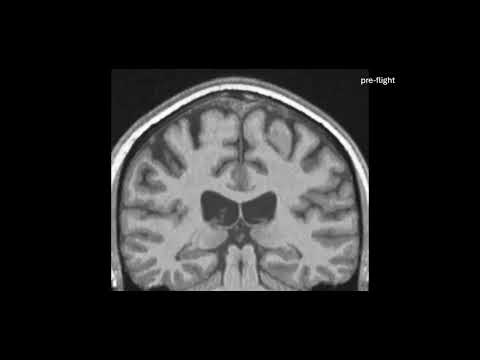

That’s not especially problematic, but it does alter how the brain sits inside the skull. Previous research has shown that the center of mass of astronauts’ brains shifts upward in their skulls after spaceflight, compared to measurements taken before spaceflight.

That’s not the only clue that things can get a little peculiar in there. A 2015 study on people confined to a tilted bed with their heads pointing downward – an Earth-based study technique to mimic the fluid redistribution effects of microgravity – also found changes not just in the center of gravity but also in the volume of certain regions of the brain.

Their detailed measurements showed that the brain shifts up and back in the skull during spaceflight, and also tilts backwards a little bit too, a tiny, subtle roll, consistent with the findings of previous studies.

However, the brain shifted in other ways, too; not uniformly all over, but with different regions changing in different directions, in a way that can’t be attributed to the movement of the entire brain.

That suggests that the very shape of the brain changes. The most pronounced shifts were observed in longer spaceflights – the brains of astronauts who spent a year in space could change by as much as two to three millimeters.

This was supported by data from the bed-tilt study, which also showed that the ventricles – fluid-filled pockets in the brain – also shift upward in microgravity and analog microgravity, strongly implicating fluid redistribution in the changes.